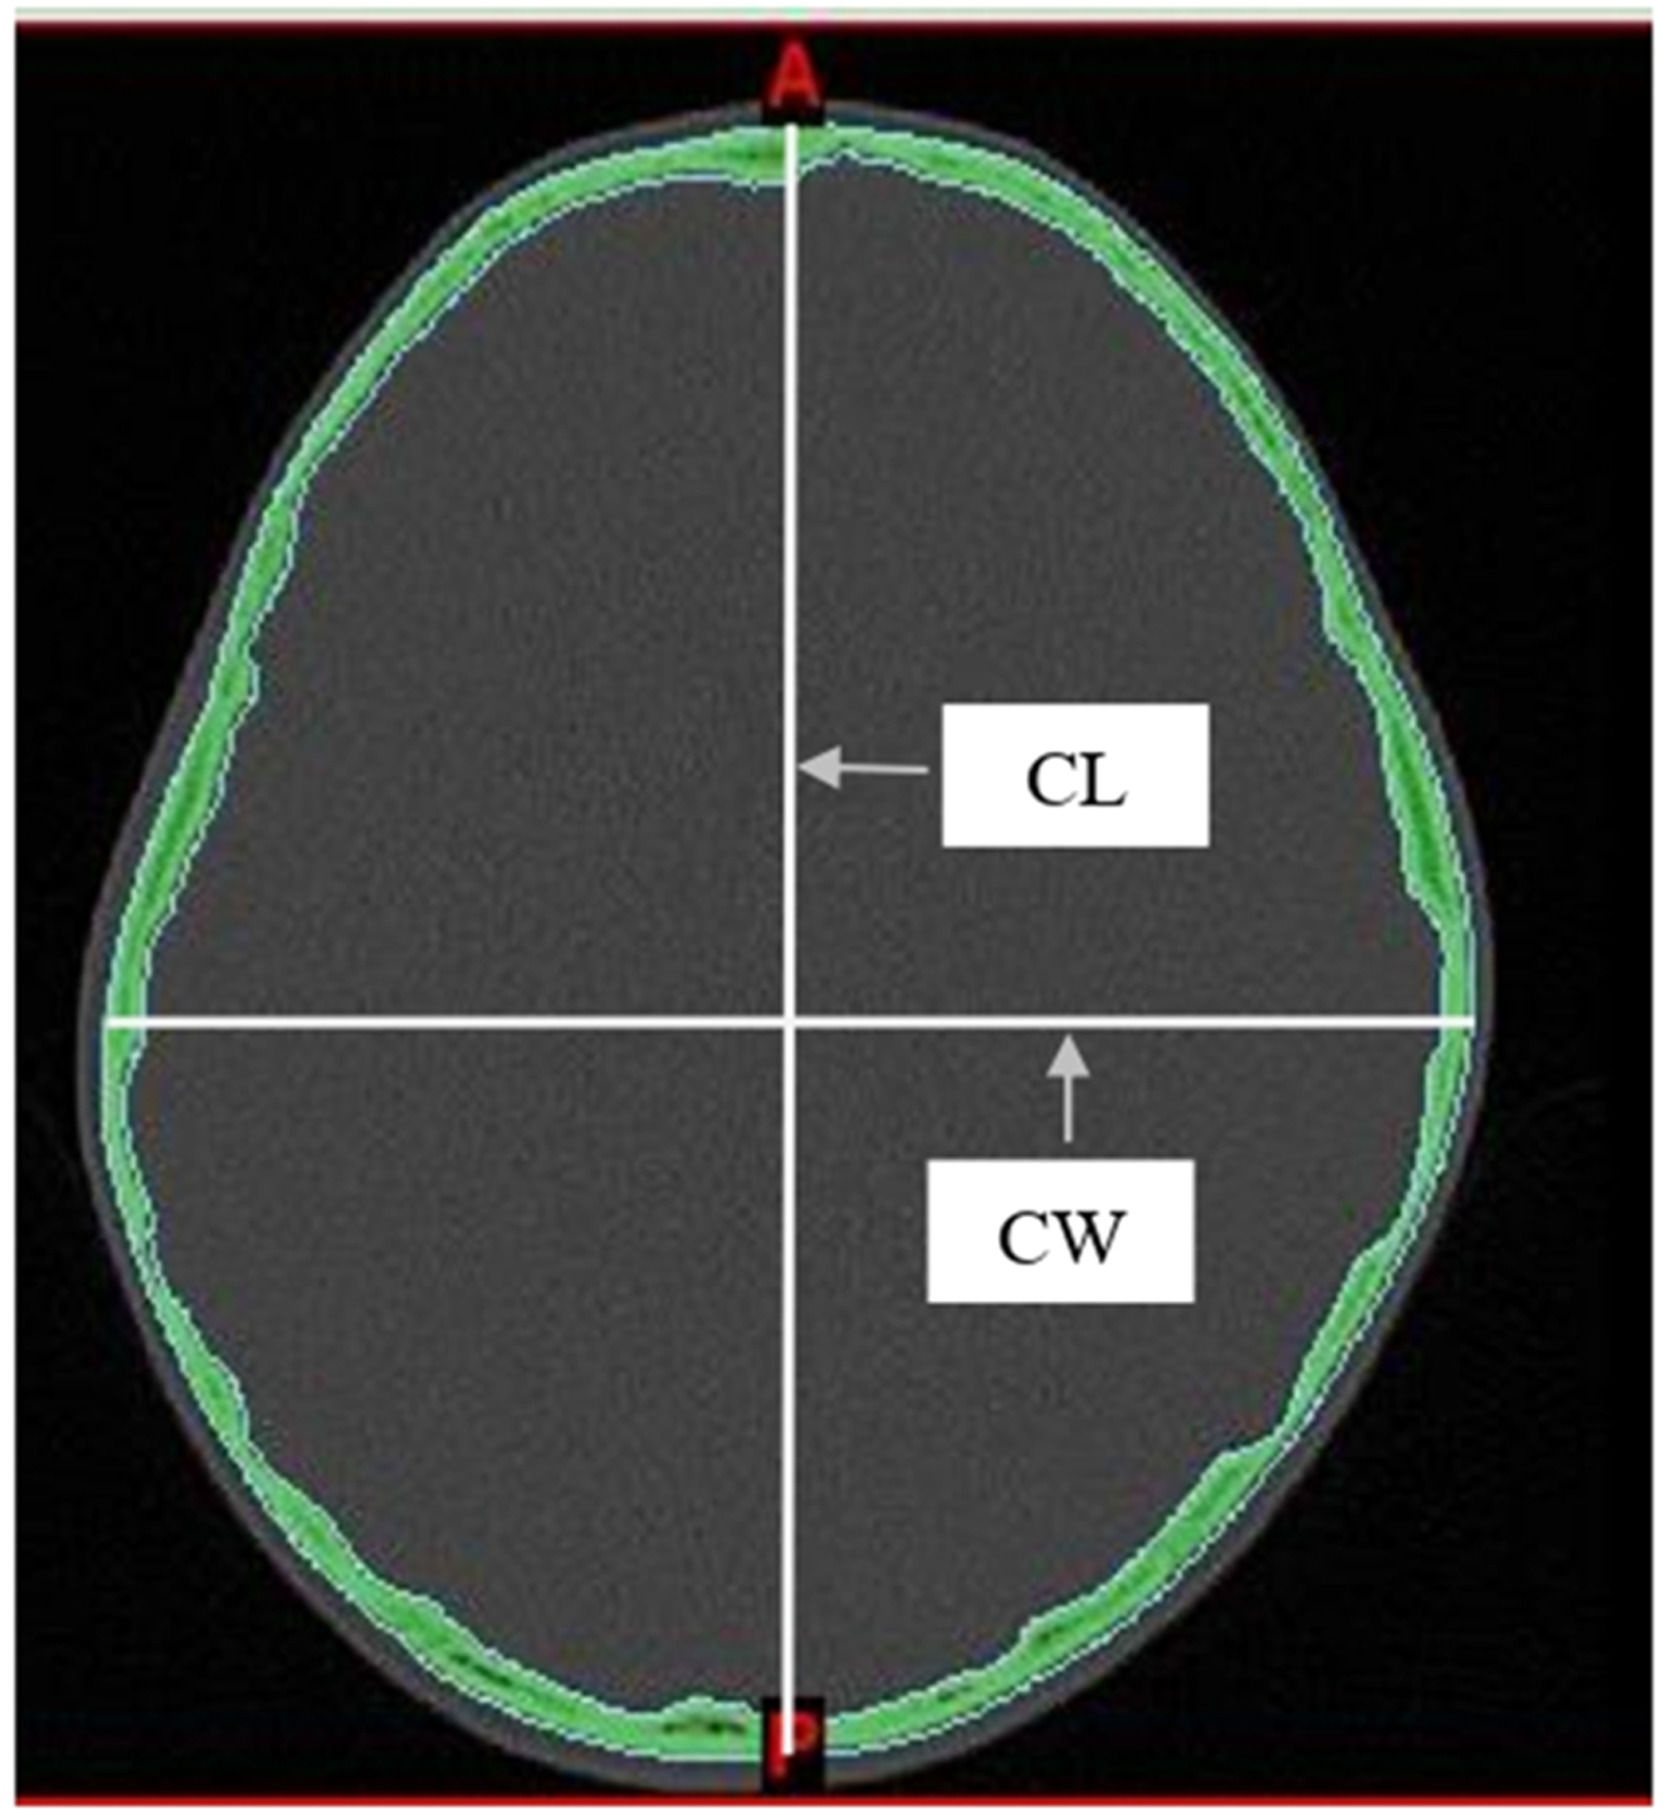

Two measurements were taken from the skull: the maximum Cephalic Length (CL) and the maximum Cephalic Width (CW). These were measured directly from axial CT images using the linear measurement tools in Mimics software. Measurements were taken on a plane parallel to the Frankfurt horizontal (auriculo-orbital) plane. Following the methods described by Waitzman et al15, all scans were assessed using established bony landmarks selected to evaluate the cranial vault. The cephalic index was then determined using the equation as follows: cephalic width/cephalic length × 100 (Fig. 1).

Fig. 1.

Measurements from axial CT scan. CL, Cephalic Length, CW, Cephalic Width. Cephalic index = CW/CL × 100.